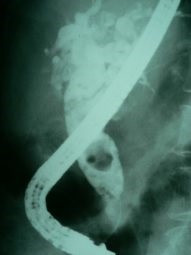

Cálculo gigante ERCP

Envíado por Dr. Carlos Miguel Zavaleta Consuegra